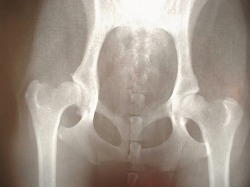

それを防ぐ意味で、本人の骨盤から骨をとって脊椎に移植したり、金属のプレートを使ってボルトで固定するといった手術が行われます。